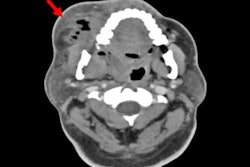

Researchers developed a hierarchical transformer model designed to improve early dental caries detection by combining multiscale feature extraction with spatial attention. Image preprocessing involved histogram equalization, bilateral filtering, and normalization to enhance radiograph quality. The transformer encoder was customized for panoramic dental images, incorporating 2D-aware positional encoding and spatially focused attention, they wrote.

Features from multiple network depths were fused using dynamically weighted aggregation, along with channel-wise and spatial attention modules to further refine lesion representation across severity levels. The model was trained and validated on a dataset of 3,856 panoramic radiographs from adult patients, including 12,847 annotated carious lesions collected from three dental hospitals between 2021 and 2023.

The model achieved a mean average precision of 87.3% across all caries stages, with sensitivities of 81.3% for D1 lesions and 84.7% for D2 lesions, outperforming both traditional CNN-based models and average dentist performance. Its advantage was most evident in early-stage detection, where it reached 79.8% average precision for D1 lesions and 82.6% for D2 lesions, exceeding all baseline methods, they wrote.

Comparison with expert annotations showed strong agreement in diagnostic outcomes. Across all severity grades, the model demonstrated an overall sensitivity of 88.4% and a specificity of 91.7% on the test set. Additionally, the system enabled real-time analysis, processing each panoramic radiograph in approximately 70 ms.